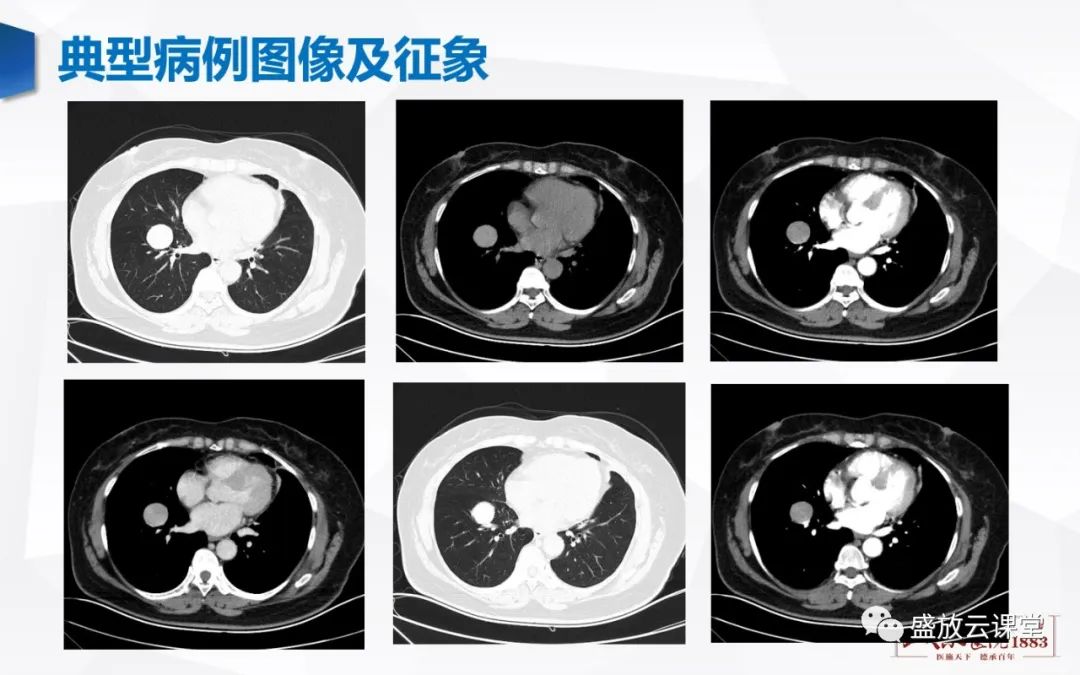

精彩图片